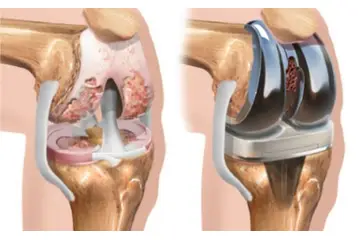

Kıkırdak dokusunun hasar görmesi durumunda uygulanabilecek çeşitli tedavi yöntemleri bulunmaktadır. Bu tedaviler arasında fizik tedavi, ilaç tedavisi (ağrı kesiciler ve anti-inflamatuar ilaçlar), enjeksiyonlar (kortikosteroid veya hyaluronik asit) ve ileri vakalarda cerrahi müdahaleler yer alabilir. Cerrahi tedaviler arasında artroskopi, mikrokırık cerrahisi ve kıkırdak nakli gibi yöntemler bulunur.

Tedavi seçenekleri, kıkırdak hasarının derecesine ve hastanın genel sağlık durumuna göre değişiklik gösterebilir. Bu nedenle, bir ortopedi uzmanına danışarak en uygun tedavi planını belirlemek önemlidir.